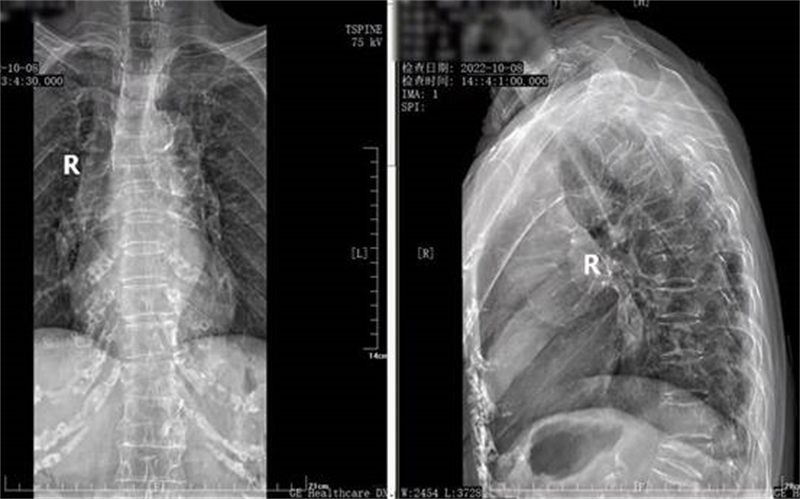

家人带她到当地医院检查后,拍片结果显示李奶奶胸6椎体骨质疏松性压缩性骨折,考虑到已过百岁的李奶奶年龄实在太大,于是决定保守治疗。然而,回家后李奶奶腰背痛的症状日益加重,无法翻身、站立,只有平躺着疼痛才能稍有缓解,家人们见状四处打听、求医,后慕名找到贺西京院长。